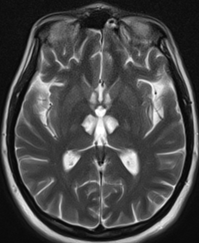

التهابُ المهادِ الإنتقائيُّ المناعيُّ ثنائيُّ الجانبِ

حالةٌ سريريَّةٌ تشي بدورٍ مُحتملٍ للفيروساتِ في تطوِّرِ وعيِ الأنسانِ

Bilateral Selective Autoimmune Thalamitis